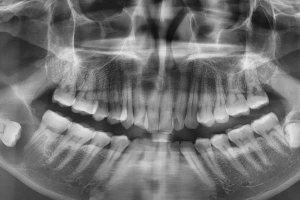

Cysts or decay detected on X-ray

Digital X-rays and advanced diagnostic tools help map the tooth’s position, nerves, and bone structure, ensuring accurate planning and minimal post-operative discomfort.

Full evaluation and X-ray to plan your tooth removal safely.